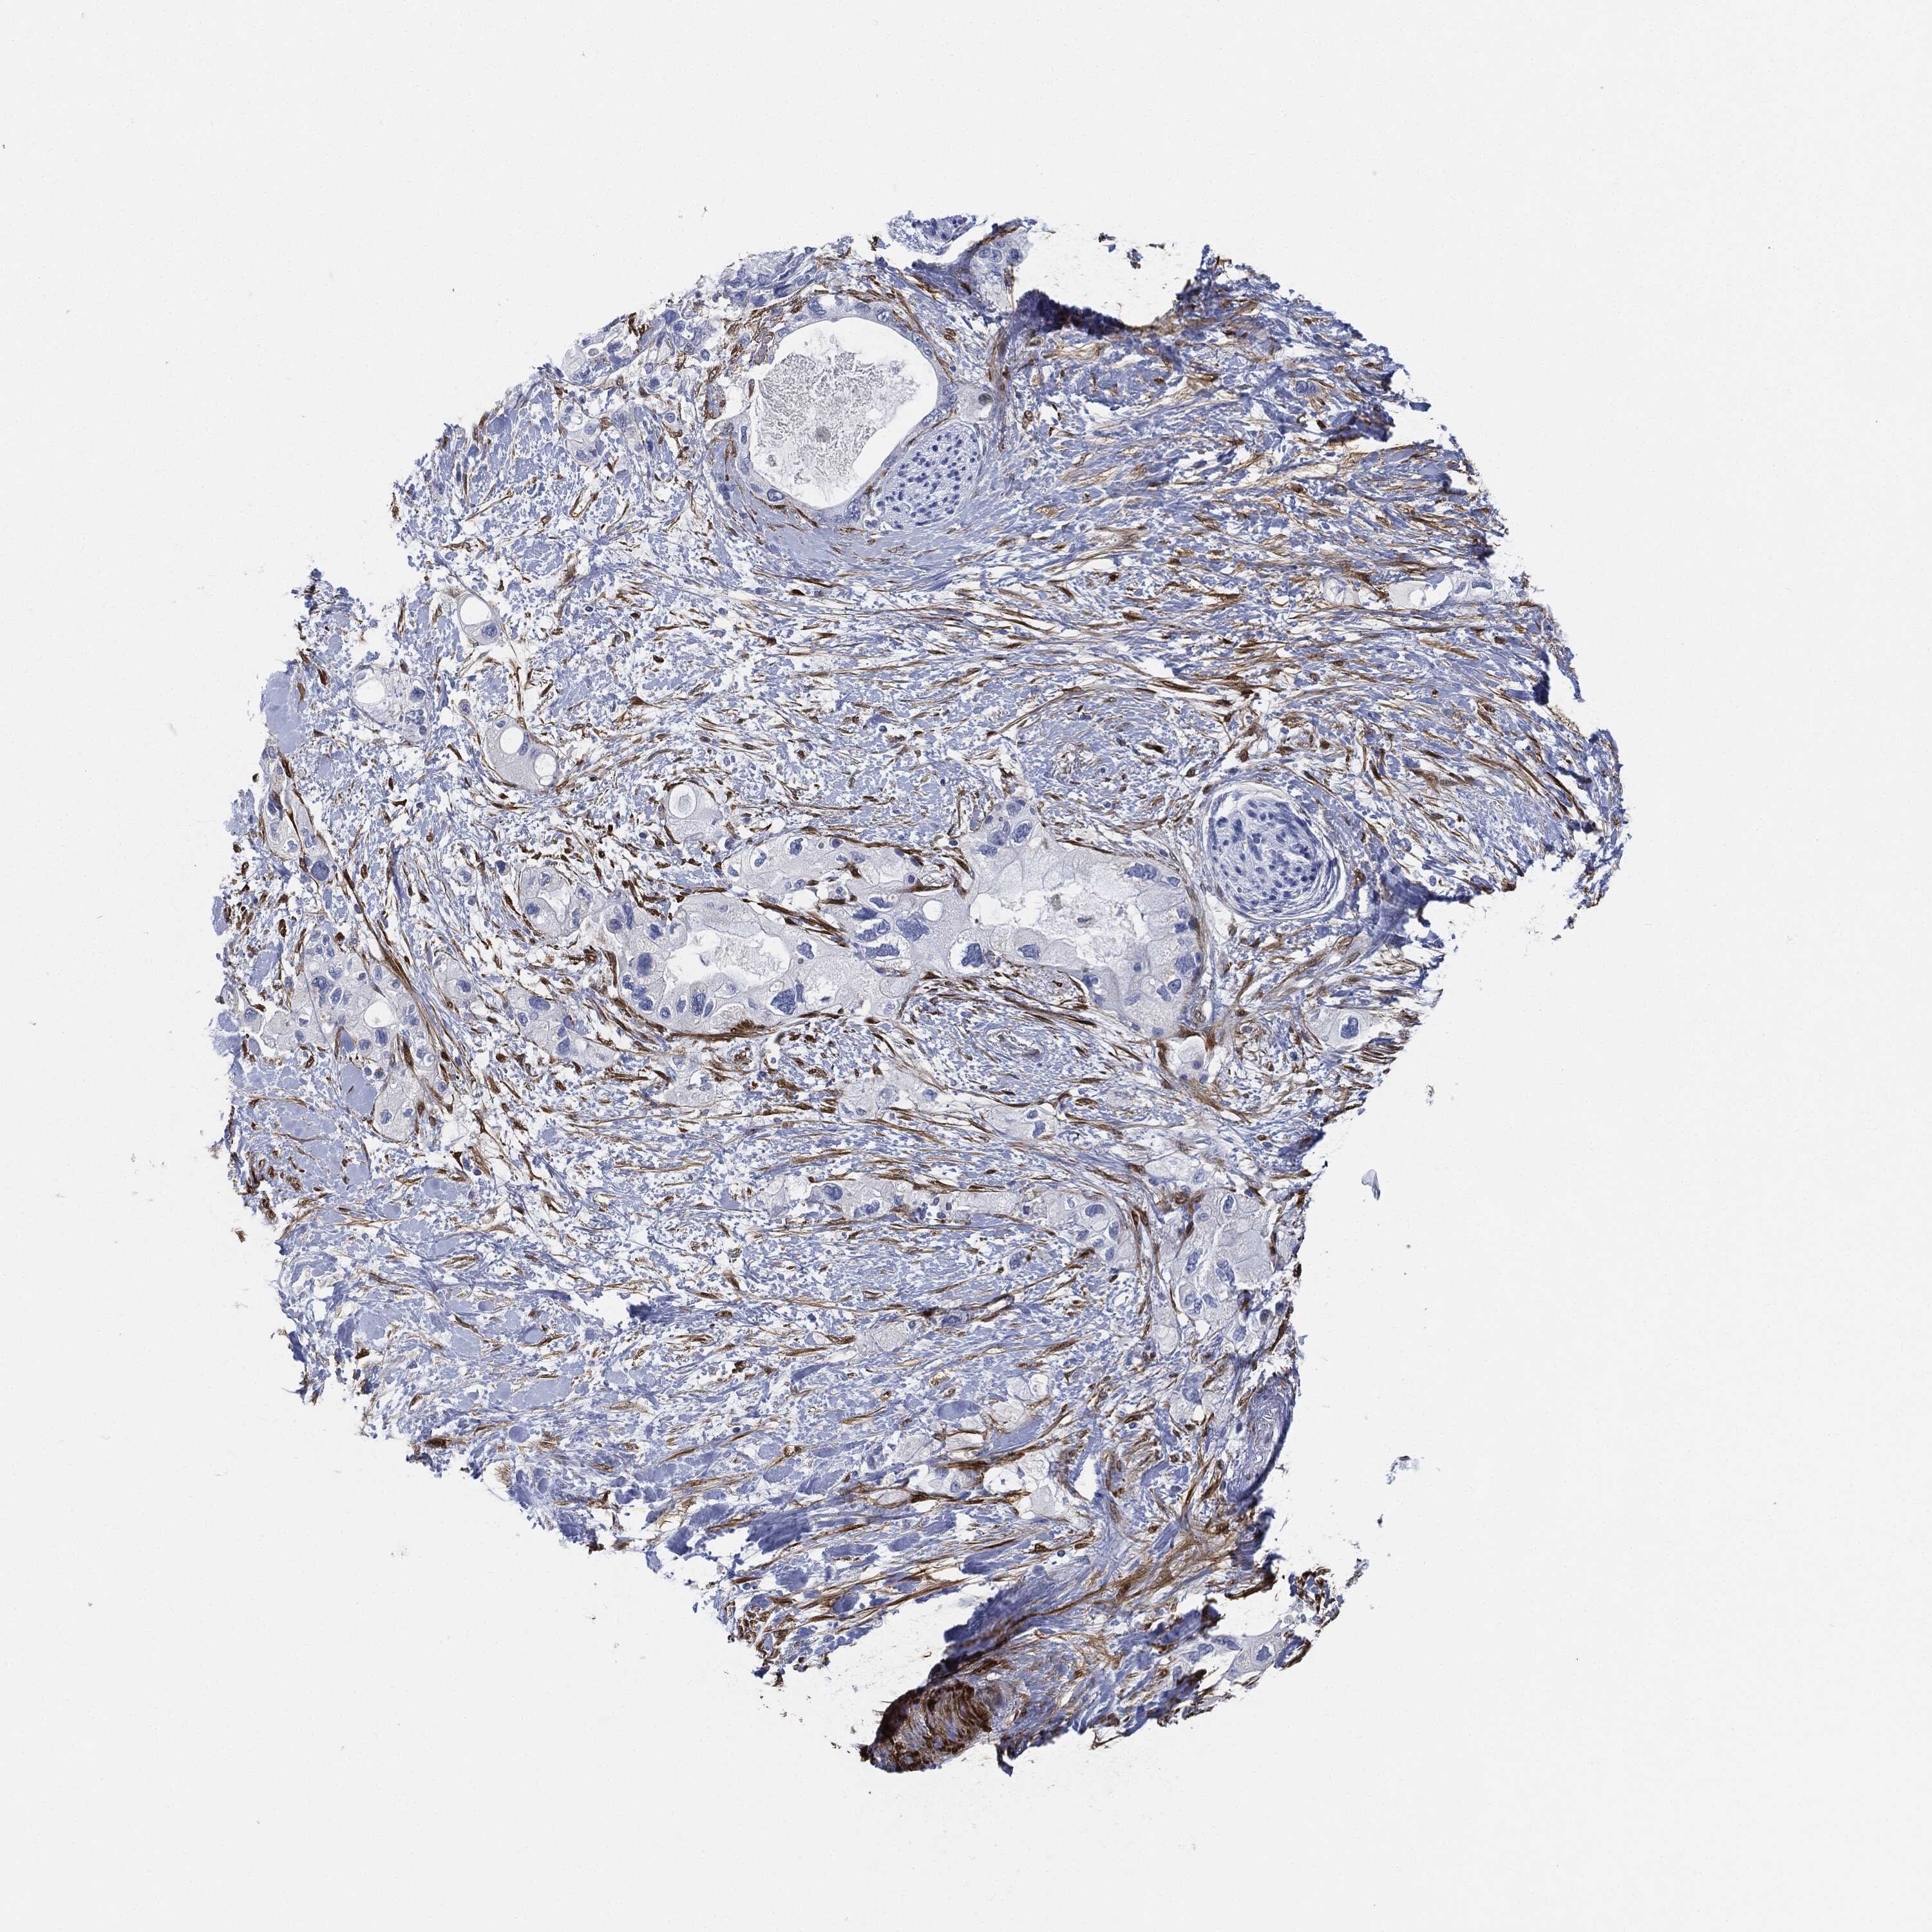

PANCREATIC CANCER - Protein expressioni

A mouse-over function shows sample information and annotation data. Click on an image to view it in a full screen mode. Samples can be filtered based on level of antibody staining by selecting one or several of the following categories: high, medium, low and not detected. The assay and annotation is described here.

Note that samples used for immunohistochemistry by the Human Protein Atlas do not correspond to samples in the TCGA dataset.

Antibody stainingi

Antibody staining in the annotated cell types in the current human tissue is reported as not detected, low, medium, or high, based on conventional immunohistochemistry profiling in selected tissues. This score is based on the combination of the staining intensity and fraction of stained cells.

Each image is clickable and will lead to virtual microscopy that enables deeper exploration of all samples and also displays staining intensity scores, fraction scores and subcellular localization as well as patient and tissue information for each sample.

Antibody HPA019467

Antibody HPA061657

Antibody CAB001447

Staining

High

Medium

Low

Not detected

Intensity

Strong

Moderate

Weak

Negative

Quantity

>75%

75%-25%

<25%

None

Location

Nuclear

Cytoplasmic/membranous

Cytoplasmic/membranous,nuclear

Adenocarcinoma, NOS